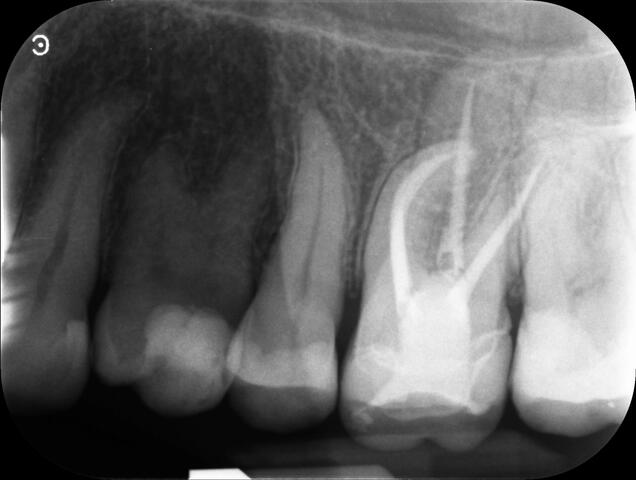

Endodontic Referrals

I am pleased to take endodontic referrals. Curved canals >30 degrees and potentially greater than 50 degrees can be negotiated. Sclerosed canals accessed. Post spaces prepared and the patient returned to you ready to restore.In most cases existing crowns, bridges and veneers can be retained with the endodontic access aesthetically restored after the full canal network has been treated.In the first instance I would prefer a radiograph and a brief list of patient expectations and a tooth history.

There are a number of ways to decide whether you need root canal treatment and the specific x-rays, scans and tests help diagnose your problem.An important sign is the type of pain you have been having with a tooth. It helps me decide if a tooth is in need of treatment and even if it saveable.

I really enjoy undertaking root canal treatments - rising to the challenge and helping people out of dental pain for the long term.I was privileged to be asked to speak at the 2016 BDA Conference, where I have a lecture about providing quality endodontic outcomes to patients, working as a generalist. Avoiding problems and pitfalls and maximising efficiency. One of the main matters that he covered was understanding that what is seen on plane radiography is utterly misleading and should not be the criteria by which a generalist continues treatment once it has been started.

At the 2016 BDA Conference, Thomas spoke about providing quality endodontic outcomes to patients, working as a generalist. Avoiding problems and pitfalls and maximising efficiency. One of the main matters that he covered was understanding that what is seen on plane radiography is utterly misleading and should not be the criteria by which a generalist continues treatment once it has been

started.